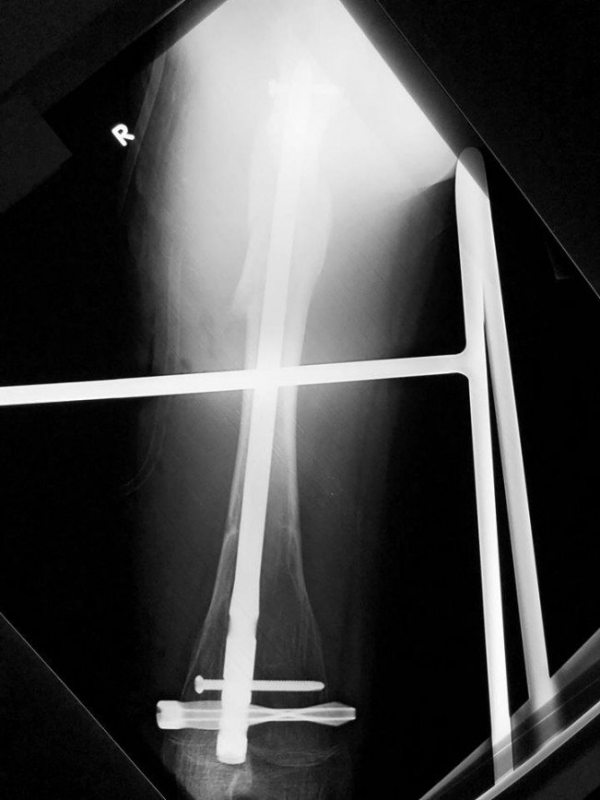

16-летний подросток ломал правую ногу всего год назад и вновь оказался на операционном столе. Медики Детской городской клинической больницы Святого Владимира соединили и зафиксировали костные отломки.

То, что метрополитен – объект повышенной опасности, знают все. Об этом не устают повторять дежурные на станциях, а объявления внутри вагонов знакомят с правилами поведения в любых экстренных ситуациях. Однако предусмотреть всего невозможно.Старшеклассник из столицы попал в Больницу Святого Владимира после поездки на метро. Мальчик упал в подземке, почувствовал сильную боль в ноге и обратился к медикам за помощью. На рентгене стало понятно: у юноши перелом правой бедренной кости. Причем всего год назад он лежал в другой больнице с точно такой же травмой. По всей видимости, кость в бедренной области еще была ослаблена, несмотря на то что в медкарте подростка стояла запись о выздоровлении.

Травматологи Сергей Баранов, Александр Васильев и анестезиолог Елена Дземешко виртуозно провели реостесинтез, сопоставив поврежденные кости с помощью специального блокируемого стержня. Он обеспечивает более эффективное срастание кости и предотвращает осложнения, так как нагрузка при движении распределяется между костью и стержнем.Уже на третьи сутки после операции юноша передвигался на костылях и даже сделал снимок с врачами-спасителями, а сейчас уже восстанавливается дома. Медики предупреждают: будьте внимательны в метро! А если в прошлом у вас были травмы, помните, что они, к сожалению, могут повториться, поэтому будьте предельно осторожны.